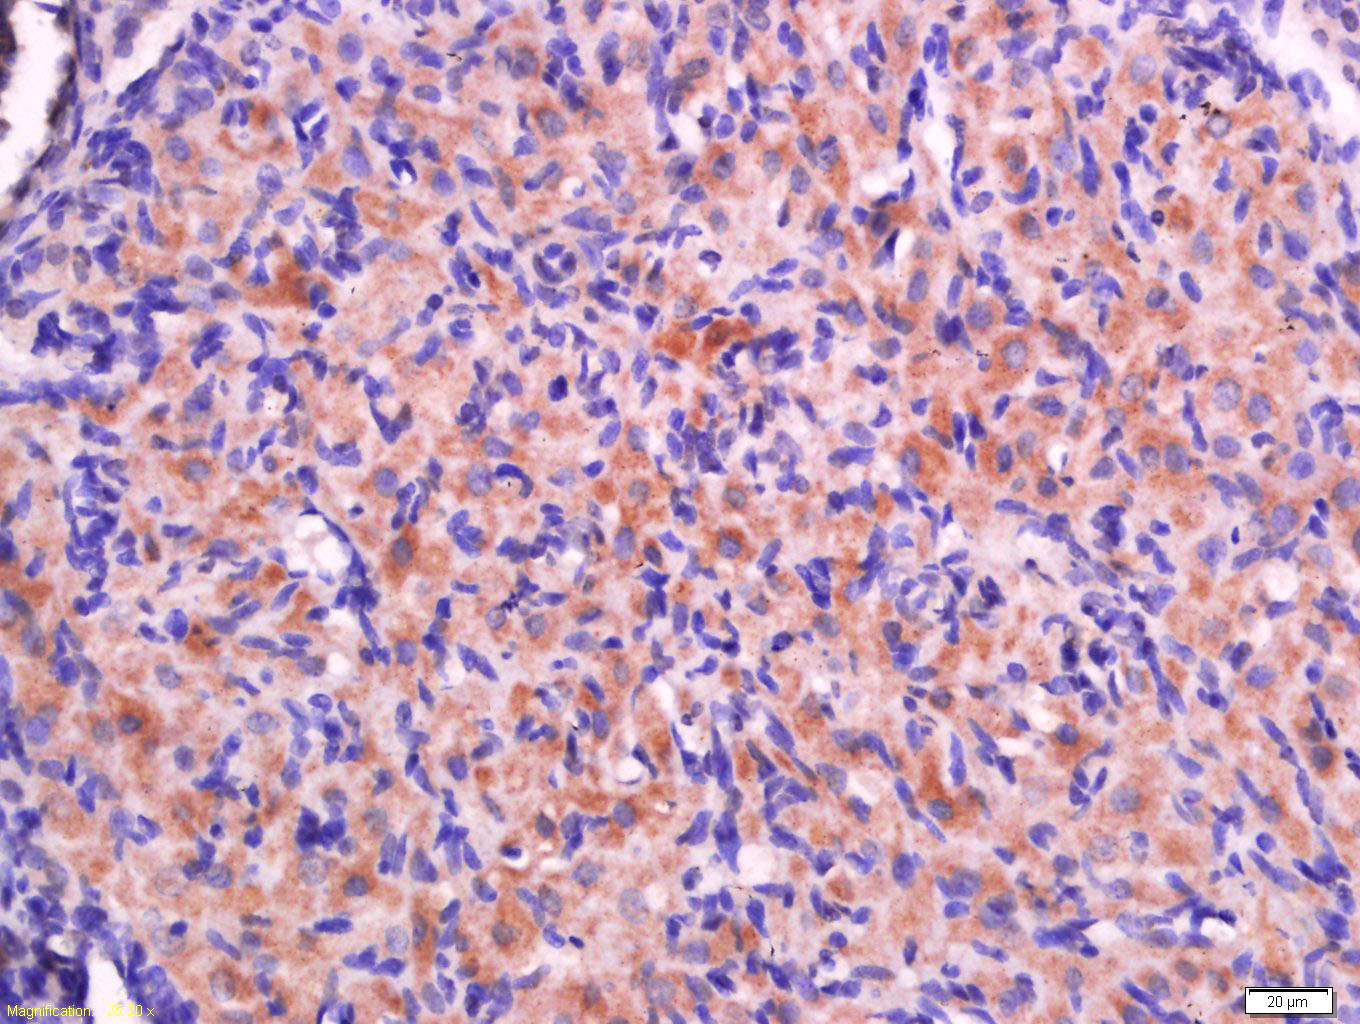

Tissue/cell: rat ovary tissue; 4% Paraformaldehyde-fixed and paraffin-embedded; Antigen retrieval: citrate buffer ( 0.01M, pH 6.0 ), Boiling bathing for 15min; Block endogenous peroxidase by 3% Hydrogen peroxide for 30min; Blocking buffer (normal goat serum,C-0005) at 37℃ for 20 min; Incubation: Anti-RPS20 Polyclonal Antibody, Unconjugated(bs-18322R) 1:500, overnight at 4°C, followed by conjugation to the secondary antibody(SP-0023) and DAB(C-0010) staining

Tissue/cell: rat testis tissue; 4% Paraformaldehyde-fixed and paraffin-embedded; Antigen retrieval: citrate buffer ( 0.01M, pH 6.0 ), Boiling bathing for 15min; Block endogenous peroxidase by 3% Hydrogen peroxide for 30min; Blocking buffer (normal goat serum,C-0005) at 37℃ for 20 min; Incubation: Anti-RPS20 Polyclonal Antibody, Unconjugated(bs-18322R) 1:500, overnight at 4°C, followed by conjugation to the secondary antibody(SP-0023) and DAB(C-0010) staining